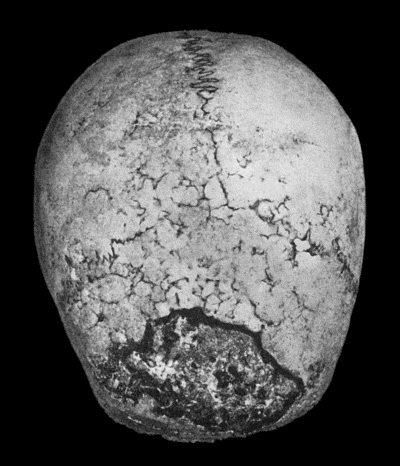

130.Syphilitic Disease of Skull 463

Weakness of the heart, as indicated by the condition of the pulse, is treated by the use of such drugs as digitalis, strophanthus, or strychnin, according to circumstances.